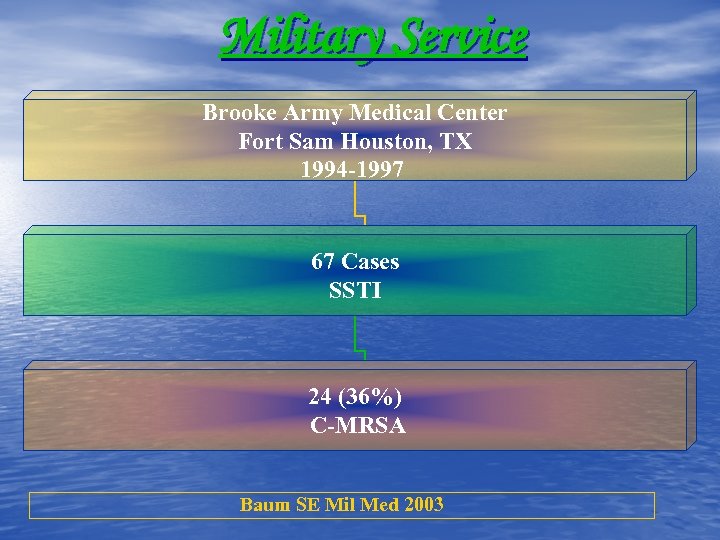

Military Service Brooke Army Medical Center Fort Sam Houston, TX 1994 -1997 67 Cases SSTI 24 (36%) C-MRSA Baum SE Mil Med 2003

Military Service Brooke Army Medical Center Fort Sam Houston, TX 1994 -1997 67 Cases SSTI 24 (36%) C-MRSA Baum SE Mil Med 2003